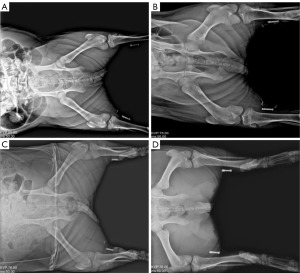

Implant stability

X-ray examinations of the implantation site conducted immediately after implantation, at 1 week, 2 weeks, and before anatomical dissection (Figure 3) revealed no displacement of the implant relative to the reference marker. The implanted device remained in its original position and operated normally throughout the observation period.

Daily, the external control unit of the TNS system was placed on the skin over the right-side electrode implantation site and activated for 1 hour. The left-side electrode remained inactive throughout the 30-day observation period and served as an internal control. This unilateral stimulation design allowed comparison between active and inactive sides in the same animal. Additionally, during stimulator implantation, an X-ray-visible non-absorbable barium core suture was secured to the soleus muscle near the electrode implantation site as a reference marker for the stimulator’s position. X-ray imaging was performed immediately after surgery to document the stimulator’s position relative to the reference marker. The operational performance of the stimulator implantation procedure was also evaluated after surgery.